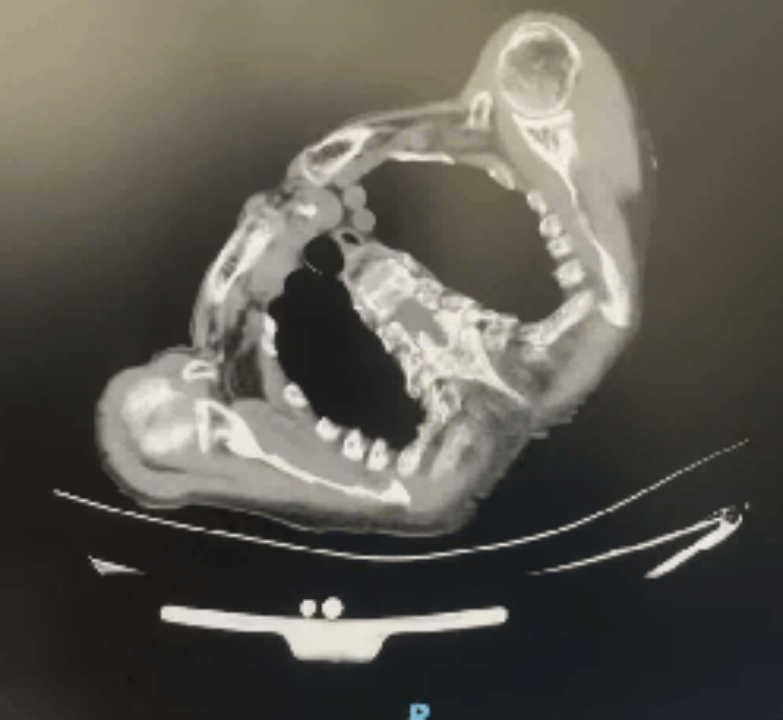

第二例患者为 82 岁女性,患有药物难治性阵发性房颤,合并肺气肿、高血压、严重脊柱侧弯 / 驼背、心脏转位及下腔静脉畸形,常规手术入路无法实施。经多学科综合评估,团队采用心电生理专科医师自主管理深度镇静镇痛方案实施手术。

脊柱畸形患者 CT 图像